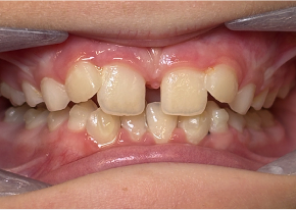

Case Report 1

10 years 0 months old, 18 stages of Invisalign Palatal Expanders

Courtesy of Dr. Sandra Khong Tai

Pre Invisalign Palatal Expander Expansion

Post Invisalign Palatal Expander Expansion

After Invisalign First treatment